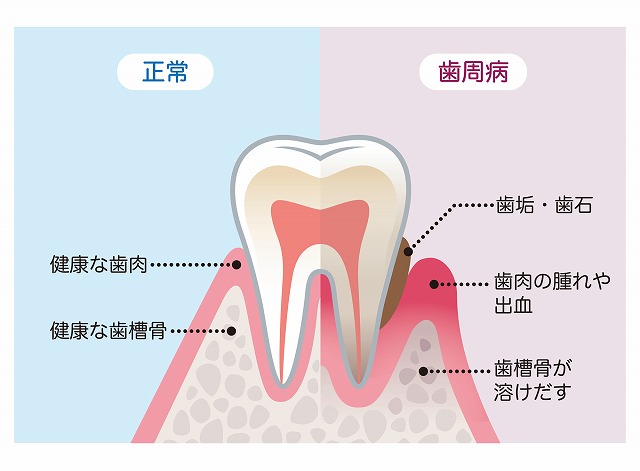

歯周病について

歯を支える顎の骨が溶け、歯ぐきが痩せてしまうのが歯周病です。

土台の機能が低下することで歯がぐらつき、最終的には抜け落ちてしまいます。近年では、治療の効果を実感しやすい治療方法も登場しています。決して諦めずに、歯周病治療に取り組みましょう。